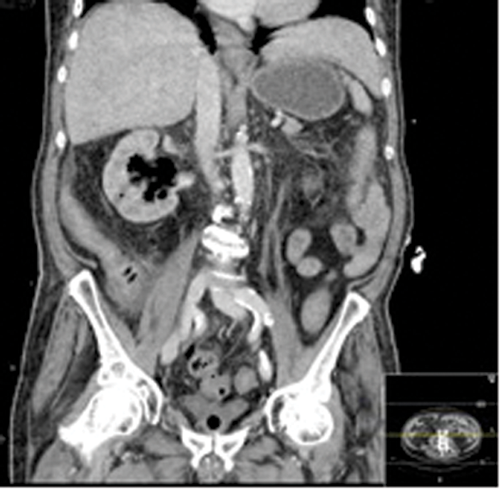

Figures 2: Patient B. Emphysematous pyelonephritis GM.